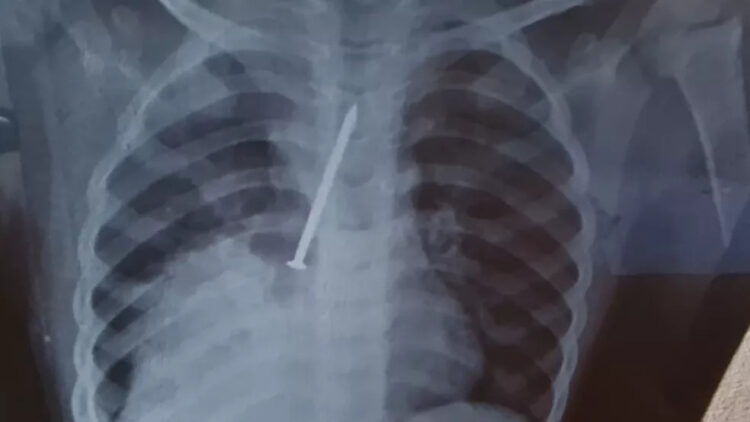

A profissional receitou medicamentos, passou uma nebulização e liberou a criança de volta para casa. Com o agravamento das dores do filho, Clarice e Cosme fizeram um exame de raio-x particular, onde identificaram a gravidade do problema do filho. A família então retornou com o garoto para o hospital.

Já no Hospital Geral do Estado (HGE), o garoto passou por uma cirurgia para retirar o prego. Os médicos identificaram que o material havia perfurado os dois pulmões de Cauan chegou a ficar internado dois dias na Unidade de Terapia Intensiva (UTI), mas ele não resistiu.

No laudo médico, a causa da morte de Cauan foi identifica como broncopneumonia. Os pais do pequeno acreditam que ele morreu vítima da negligência nos atendimentos médicos no Hospital Municipal de Canavieiras.